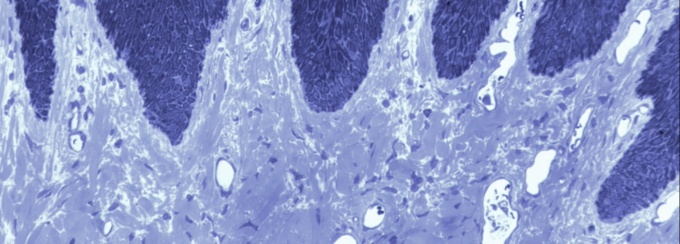

Our lab is focused on pathogenic strategies of periodontal bacteria, investigating how periodontal pathogens undermine host innate immunity.